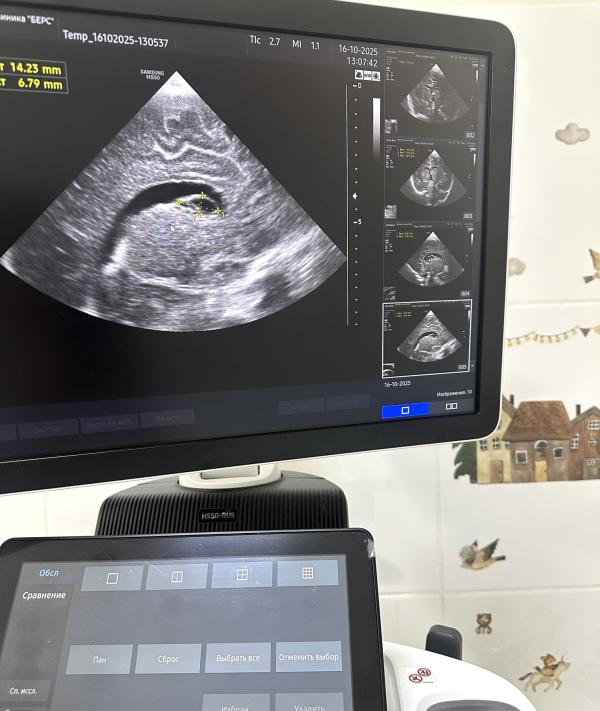

На УЗИ вчера был абсолютно здоровый доношенный малыш, роды естественные, в срок. Единственным моментом стало то, что нейросонография проводилась в возрасте двух месяцев, и мама слегка расстроилась, узнав о наличии кист и небольшом расширении боковых желудочков.

*на узи-снимках указаны кисты и их измерения